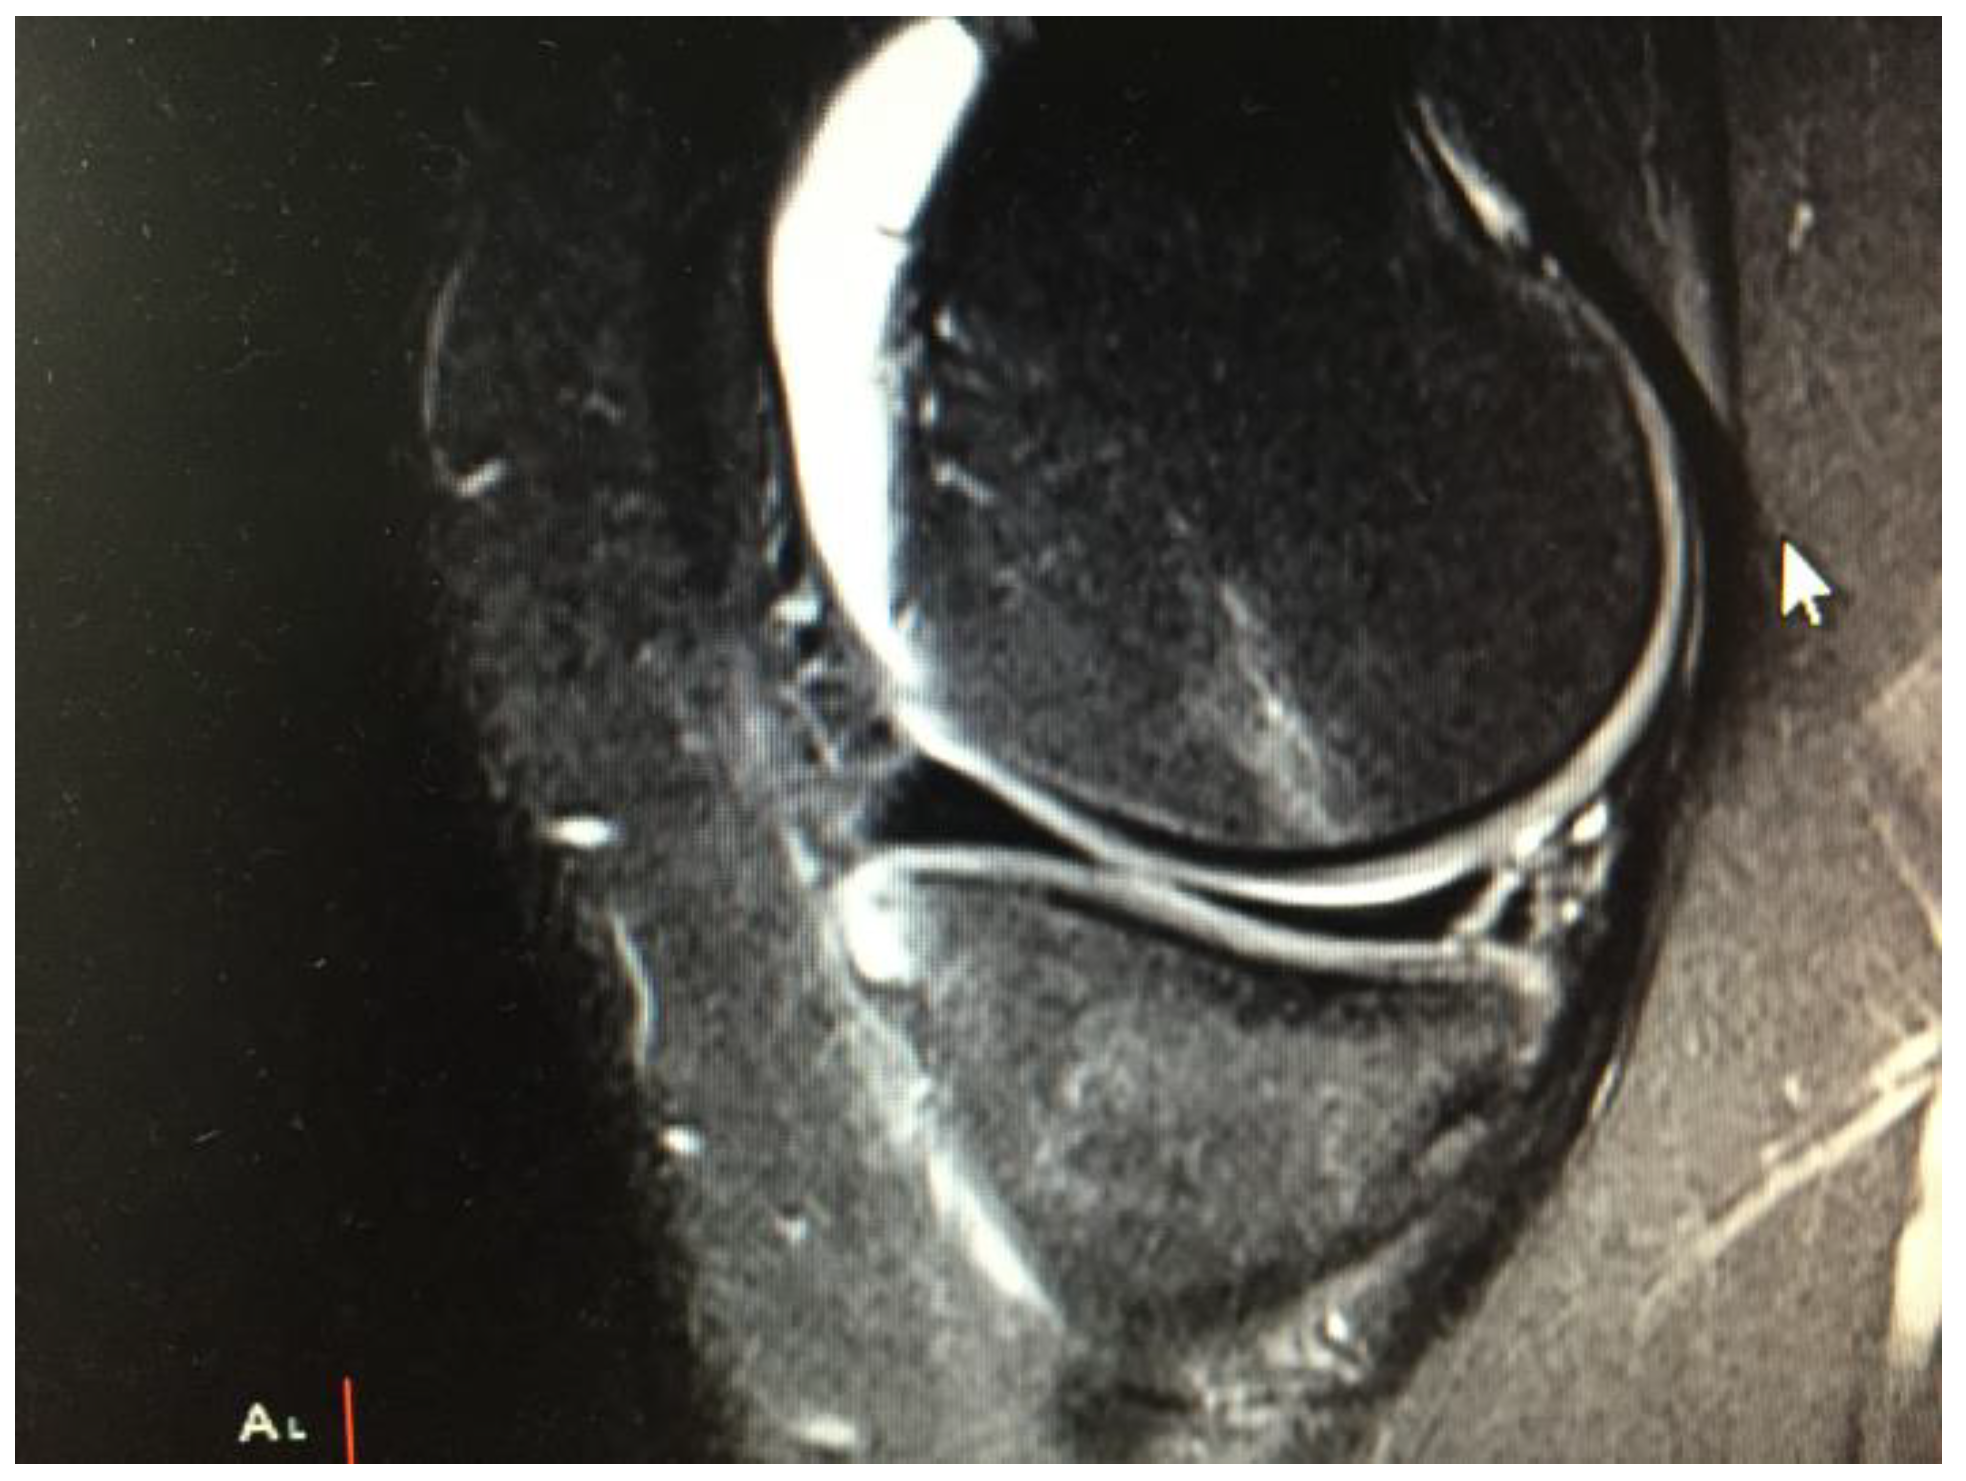

2.2. Surgical Technique